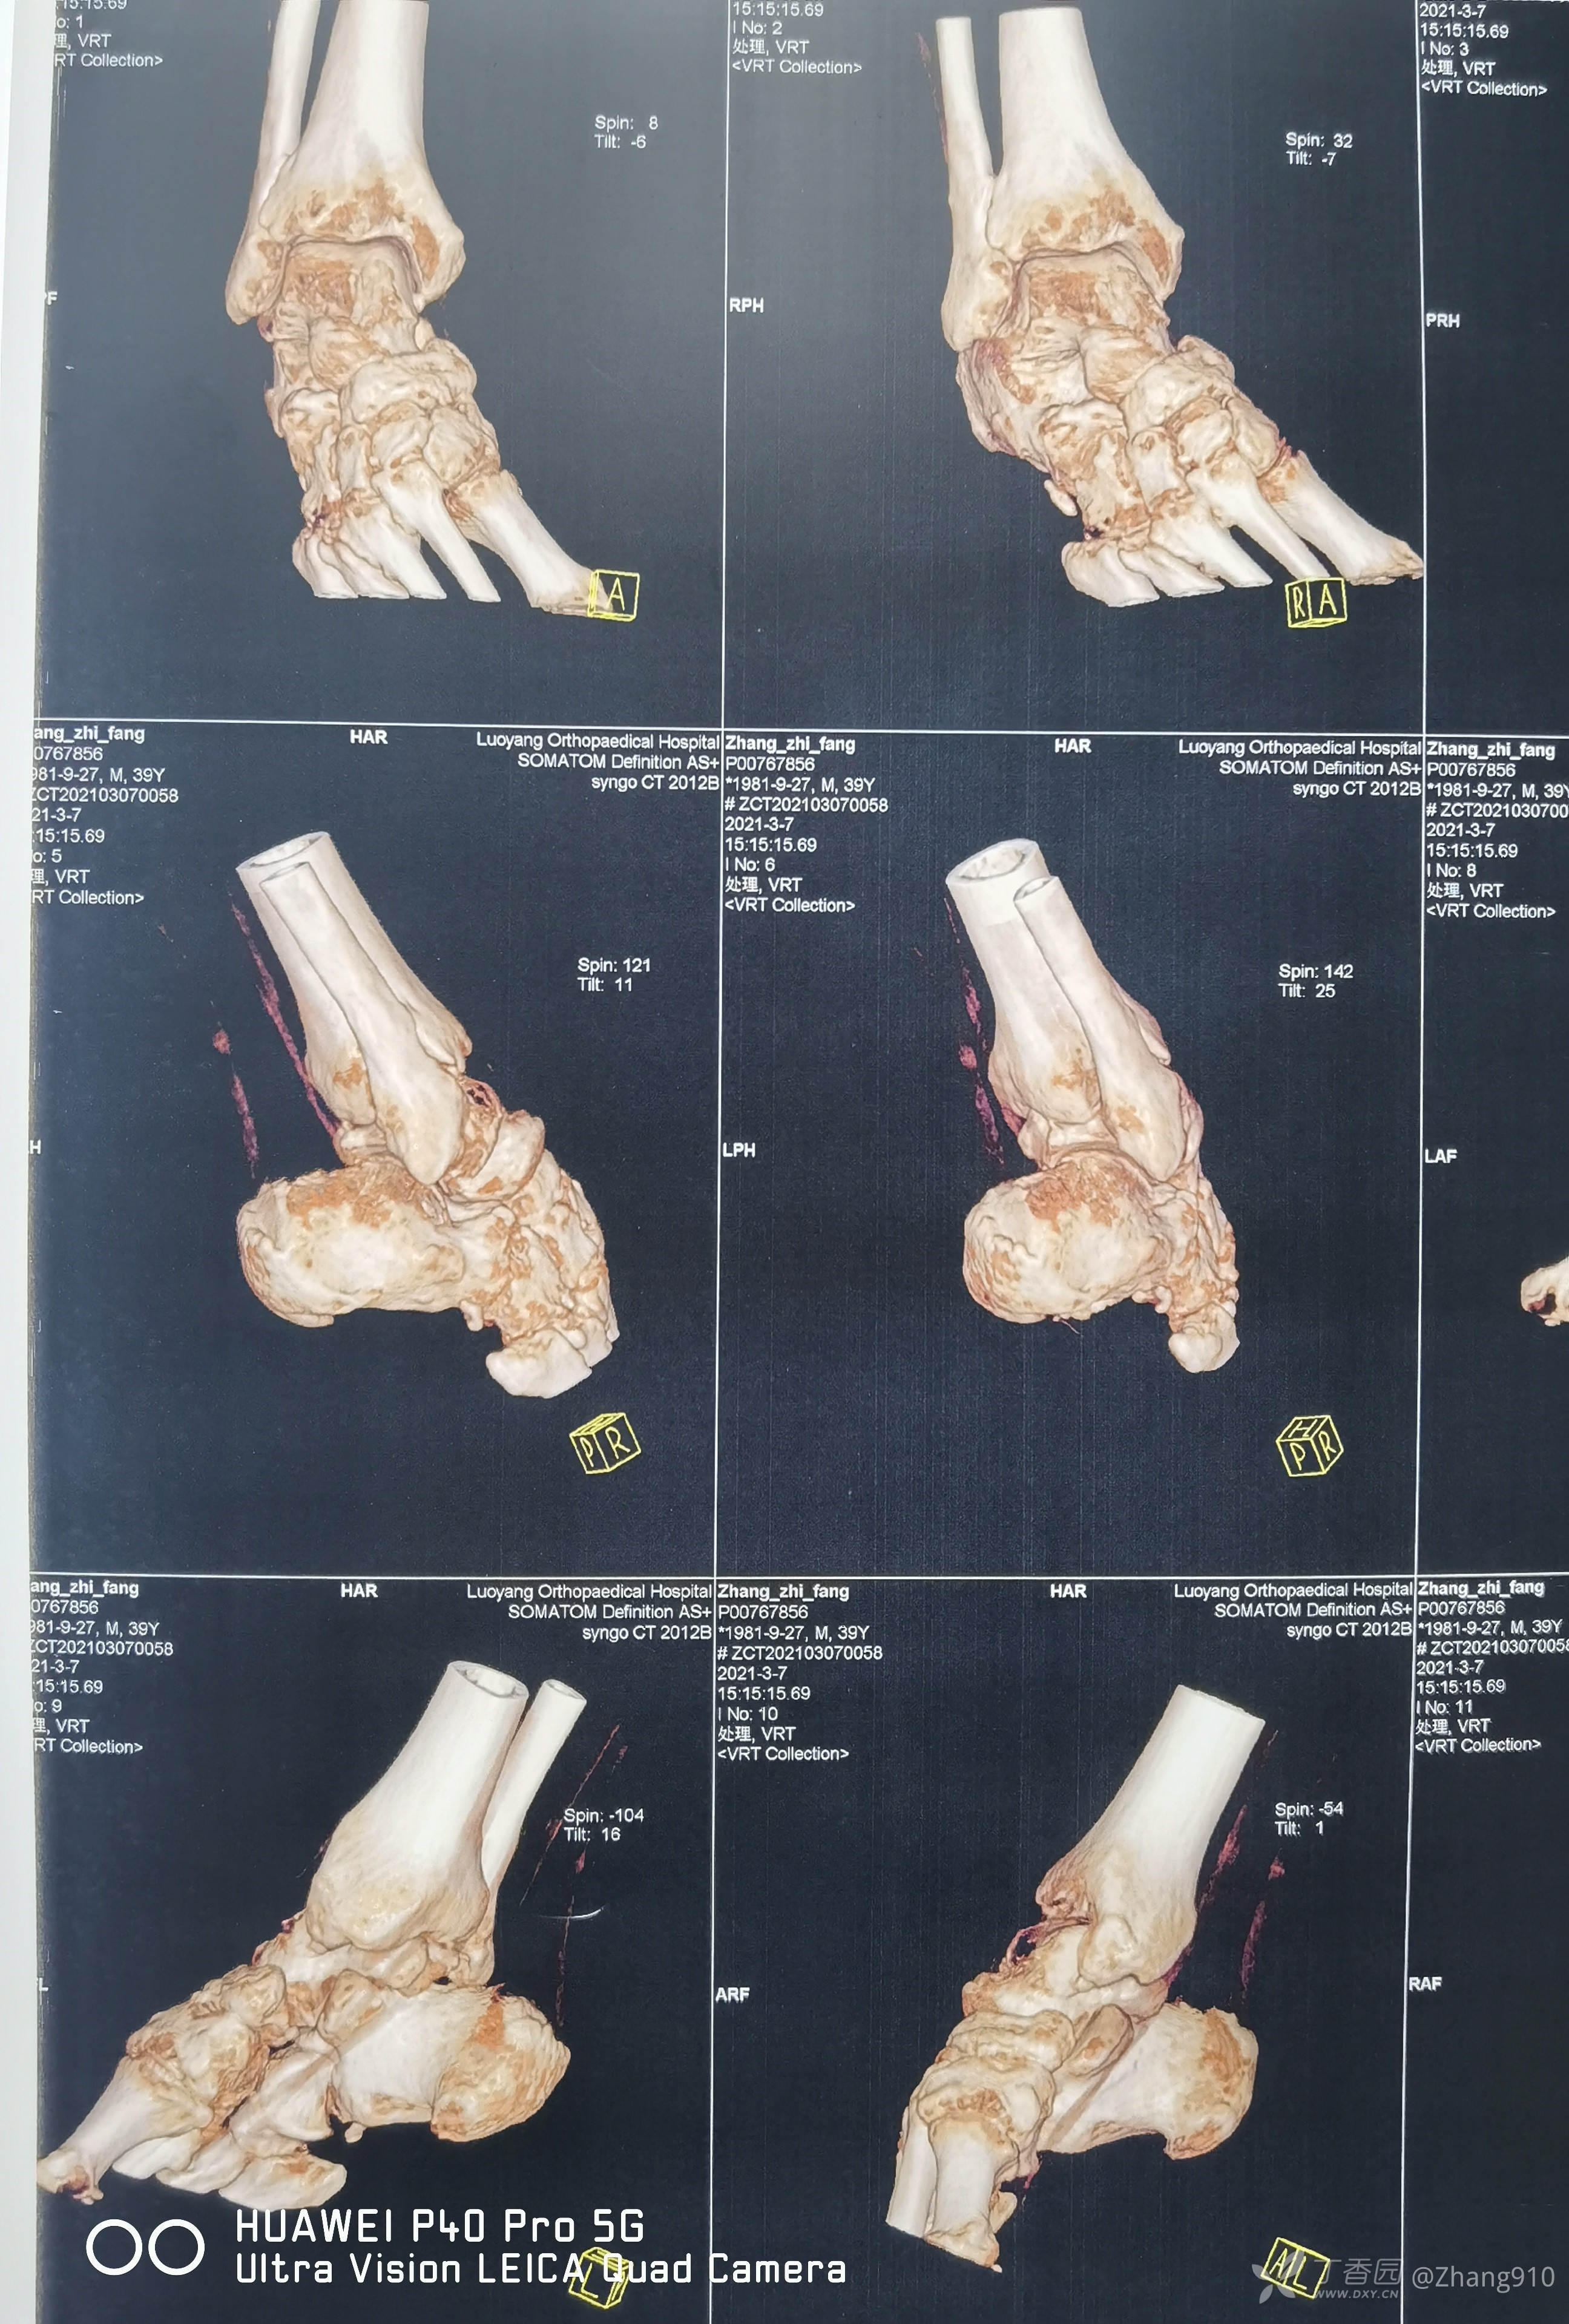

于2021.03.07

入住D院(省三甲医院,足踝外科)

入院辅助检查:

行:关节融合术。